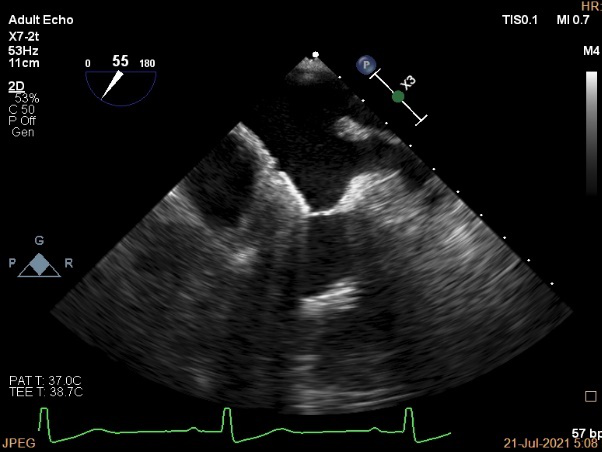

术中超声引导:

确定房间隔穿刺点:靠后

穿刺点高度测量:4.14cm

2D视图下测量大鞘长度2.2cm

2D视图下建立trajectory

3D视图打开夹子

3D视图下调Rotate,定位2区

X-plane:下夹子尝试捕获2区

夹子逐渐夹闭后,2区返流逐渐减少

3D:测量前叶长21.2mm,后叶长10.2mm

X-plane:计算前叶捕获长度6.8mm,后叶捕获长度6.5mm

夹子放置后二尖瓣口平均跨瓣压差:3mmHg

肺静脉血流频谱恢复正常

3D视图下观察二尖瓣双孔形态

3D-color:残余少量返流